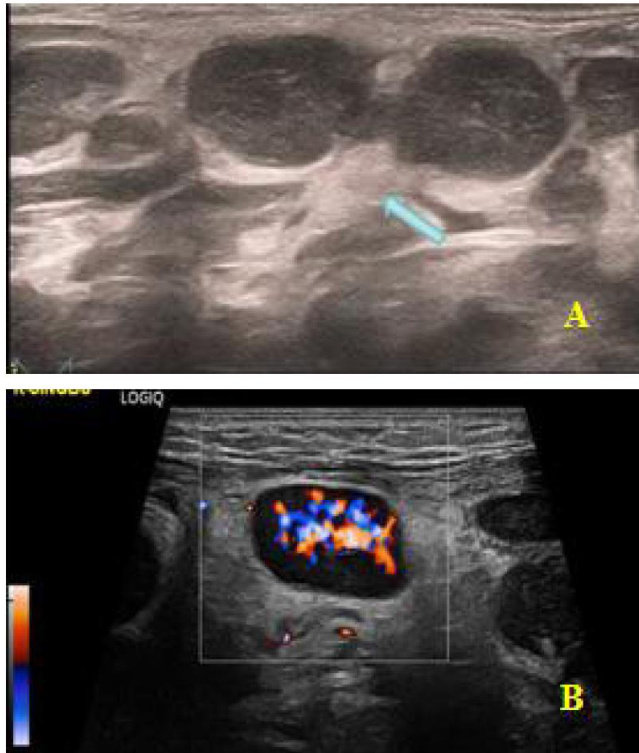

【摘要】目的分析儿童组织细胞坏死性淋巴结炎(HNL)颈部淋巴结及相关受累部位的超声特征。方法回顾性分析2022年5月至2025年5月河南中医药大学第一附属医院收治的HNL患儿的临床资料,观察并记录异常部位淋巴结超声特征。结果共纳入33例HNL患儿,均存在颈部淋巴结肿大,以单侧受累为主( 60.61% )。 69.70% 患儿受累淋巴结呈类圆形串珠样有序分布, 72.73% 患儿淋巴结周围组织回声增高, 72.73% 患儿淋巴结内部回声为均匀减低, 30.30% 患儿淋巴结伴融合倾向,部分患儿可合并其他部位淋巴结肿大及肝脾肿大。彩色多普勒显示所有患儿淋巴结血流信号呈门型分布,且以丰富血流信号为主( 69.70% )。结论超声检查有助于儿童HNL的早期诊断和病情评估,为临床提供更多有效影像学依据,有助于优化儿童HNL的诊疗路径,指导穿刺活检与临床决策。